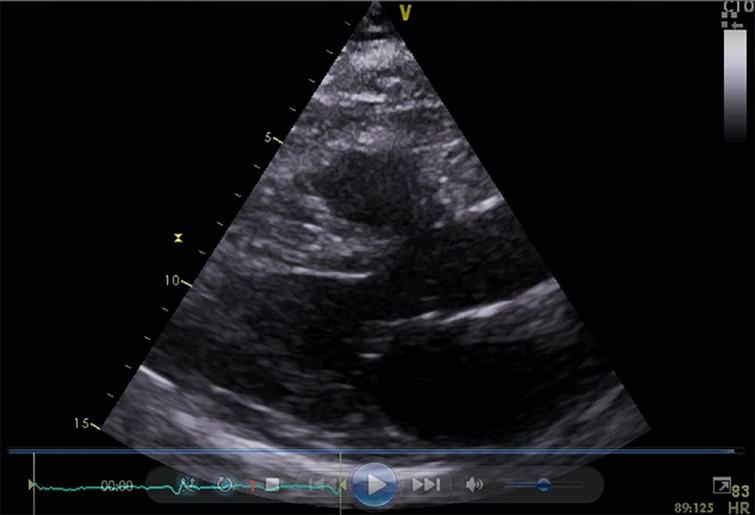

A 55-year-old female patient presented to the endocrine clinic with Grave's disease. She was initially treated with carbimazole. After an early relapse, a decision was made to proceed with radioactive iodine therapy. Four days after radioiodine administration, she presented to the emergency department with chest tightness and dyspnea due to heart failure. Biochemistry revealed thyrotoxicosis and significantly elevated Troponin-T. There was ST segment elevation on electrocardiography. However, coronary angiography was normal. Ventricular function was fully restored after 6 weeks of supportive medical management. A diagnosis of stress cardiomyopathy following radioactive iodine therapy was made. This is the second case reported in the literature so far to the best of our knowledge.

Stress cardiomyopathy in the context of radiation thyroiditis is a rare complication following radioiodine therapy. A degree of awareness is essential because the approach is multidisciplinary. Management is mainly supportive and cardiac dysfunction is completely reversible in most cases. The pathogenesis of this condition remains unclear. Post-menopausal women and susceptible individuals appear to be pre-disposed.